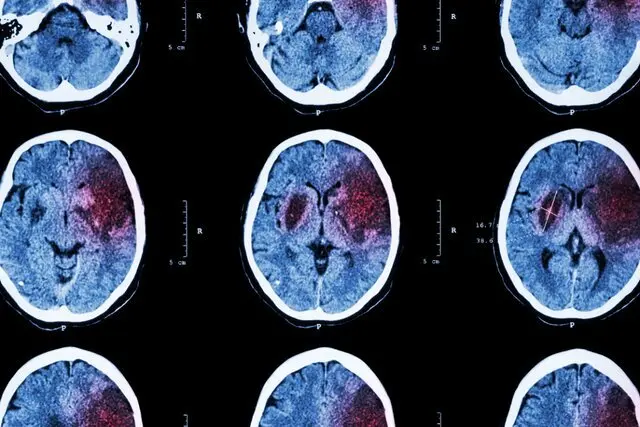

سکته مغزی، دومین علت مرگ در ایرانیها

سکته مغزی یکی از علل اصلی مرگ و میر در جهان محسوب میشود و نه تنها برخی از مبتلایانش را به کام مرگ میکشاند، بلکه افراد بسیاری هم در اثر این عارضه دچار ناتوانیهایی میشوند که تا پایان عمر همراه همیشگی آنها است…

سکته مغزی دومین عامل مرگ و میر ایرانیان

عضو هیاتعلمی دانشگاه علومپزشکی شهید بهشتی، درباره مرگومیر ناشی از سکته مغزی نیز گفت: مطالعات متعددی درباره مرگومیر ناشی از سکته مغزی در دنیا و ایران در دسترس است. سکته مغزی، دومین تا پنجمین علتی است که سبب مرگومیر مردمان کشورهای مختلف میشود و جزو علل اصلی ناتوانی به حساب میآید. براساس آمار و ارقام «سیمای مرگ ایران»، متاسفانه سکته مغزی پس از سکته قلبی سبب مرگومیر مردم کشور میشود.